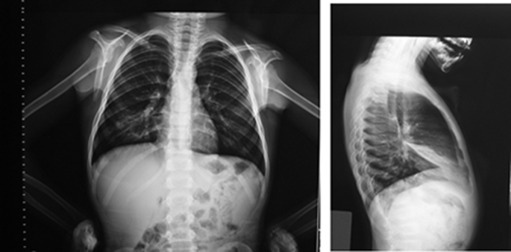

In this prospective study, children between the ages of 3–18 years with an initial diagnosis of asthma who had developed RML atelectasis during follow-up (Fig. 1) were enrolled from the outpatient allergy clinic of the Ankara Education and Research Hospital. The initial diagnosis of asthma was established if there had been a history of respiratory symptoms, such as intermittent wheezing, shortness of breath, coughing, and/or reversible expiratory airflow limitation, defined by at least a twelve percent improvement in forced expiratory volume in 1 s (FEV1) following bronchodilator administration.9 As part of a routine clinical practice, before making an initial diagnosis of asthma the patients who participated in this study had been evaluated for the other etiologies of recurrent respiratory symptoms with other diagnostic tools including chest X-rays and none of them had been found to have any structural pulmonary abnormalities at that time. In this study the chest X-rays revealing atelectasis during follow-up had been required either due to symptoms where we suspected uncontrolled asthma or due to the existence of an exacerbation. In that case, the diagnosis of RML atelectasis was based on radiologic findings, more apparent in the lateral view of a chest X-ray as a wedge-shaped, increased density between the minor and major fissures, with the apex at the hilum and the base towards the pleura10 (Fig. 1). Patients were excluded from the study if they had severe, predefined chronic illnesses other than asthma, including cystic fibrosis, primary ciliary dyskinesia, chest wall defects.

Posteroanterior and lateral radiographs of five-year-old child with atelectasis of right middle lobe.